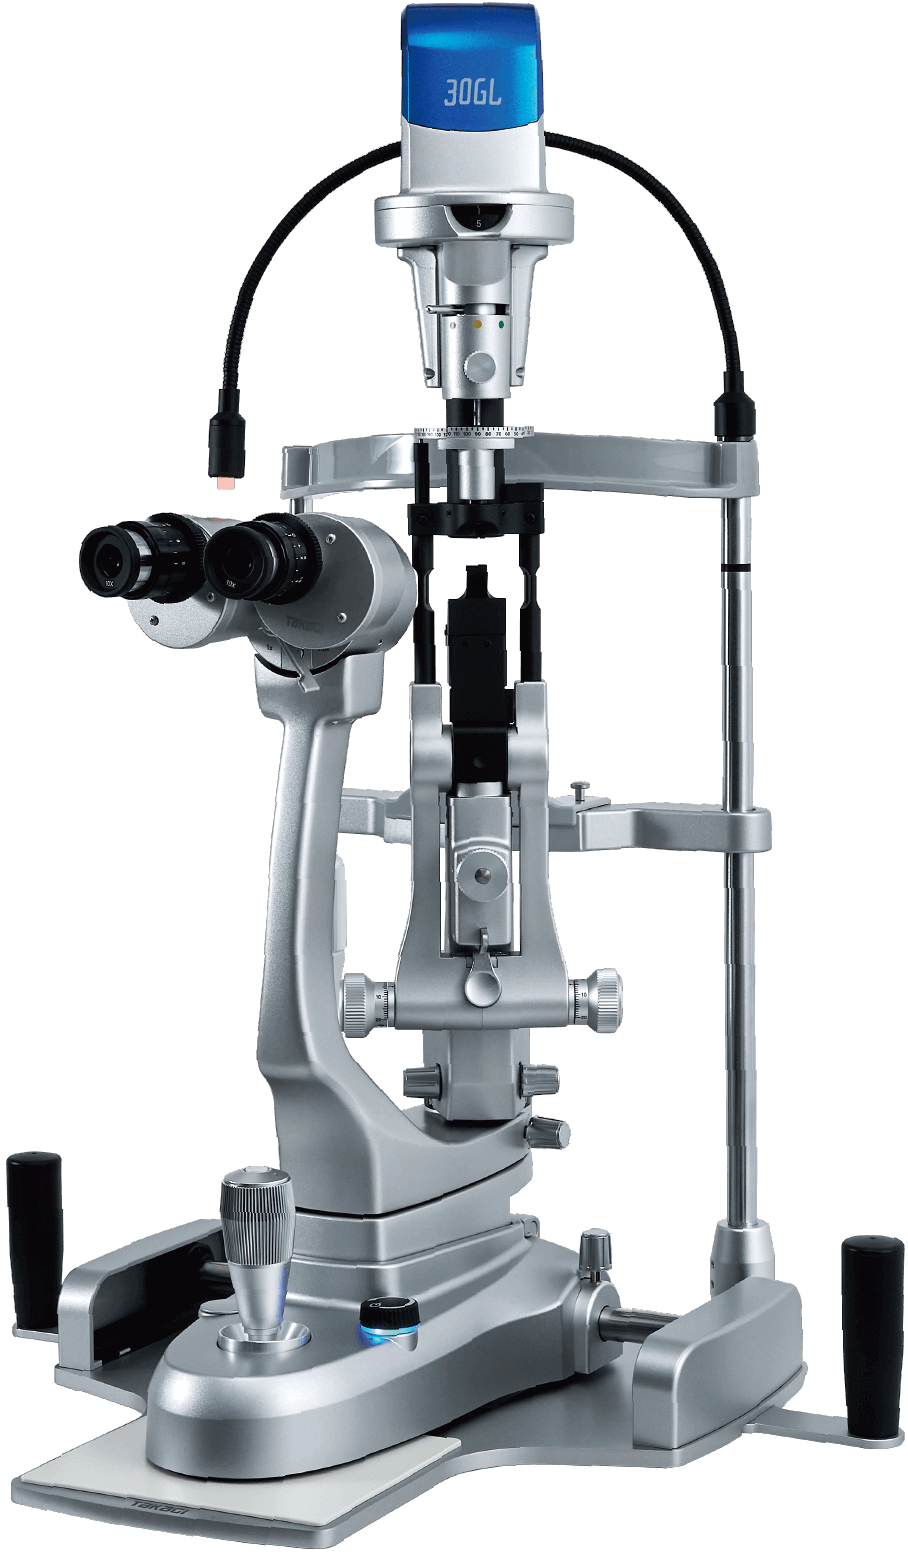

Slit Lamp Microscopes

30GL

●Design optimized for everyday medical environments

●Greenough optics deliver a stereoscopic field of view

●Intuitive and smooth operations

The 30GL is equipped with a Greenough microscope which provides rich stereoscopic images that are easy to fuse, helping to accurately identify the condition of affected areas. Combined with a high-luminance LED light source, it ensures a bright and clear view.

To reduce the burden on doctors during long examinations and minimize fatigue, the design focuses on ease of use, from the size and positioning of the operating parts to their operational feel. The simple optical structure results in intuitive operations. This model is ideal for facilities that prioritize cost-effectiveness.

This model uses an energy-saving LED light source which provides stable brightness over a long service life. This allows a design with built-in cables and reduces heat generation, contributing to enhanced patient safety.

The high-luminance LED delivers natural color and clear imaging, contributing to comfortable examinations and enhanced diagnostic accuracy.

This provides a deeper three-dimensional image, enabling clear visualization of fine fundus structures. A comfortable observation environment supports examination quality.

The 30GL adopts a Greenough microscope with a stereo angle of approximately 13°. Because the inward angle of the eyes is nearly the same as when not using a microscope, it provides a natural, easy-to-fuse stereoscopic view, allowing for comfortable observation even over extended periods.

In addition to high optical performance, features such as magnification switching via a zoom lever and brightness adjustment are designed with operability in mind, supporting efficient examinations.